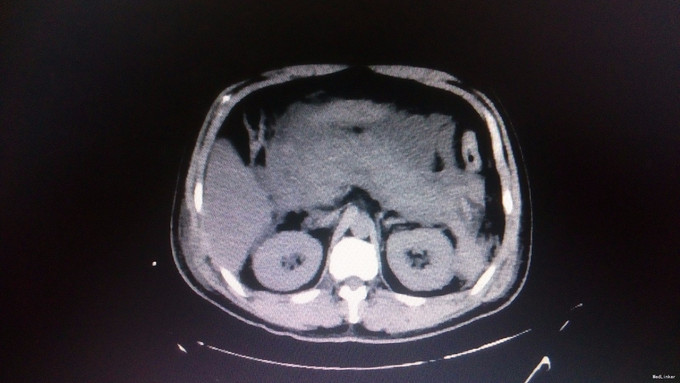

查体:腹部膨隆,全腹压痛反跳痛,四肢无力。体温39。8摄氏度,心率110左右,血压110/70mmHg。 辅助检查:入院后急查提示淀粉酶126,脂肪酶185.5,血钾2.02,钠172.9,钙1.76。腹部CT提示双下肺炎症,双侧胸腔少量积液。胰腺符合急性胰腺炎改变。